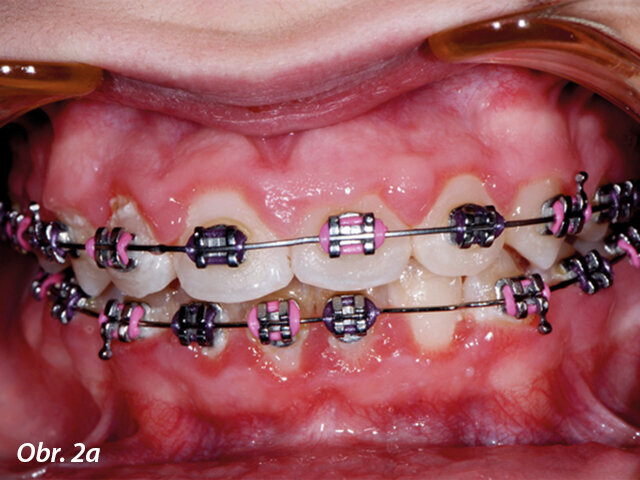

Gingivoplastika kvůli optimálnímu umístění zámku.

Gingivoplastika

Částečně prořezaný zub může často zpomalit průběh celé terapie. Recontouring dásní umožňuje správné umístění zámku a okamžité zahájení zařazování zubu ortodontickým aparátem. Nedostatečně prořezaný zub částečně krytý gingivou může být častěji postižen dekalcifikacemi, protože v průběhu terapie pacient není schopen vyčistit sklovinu v místě gingivální hyperplazie. Odvápnění v obtížně dostupných oblastech může ohrozit výsledky celé léčby. Po ukončení ortodontické terapie mohou být pro zlepšení estetiky laserem odstraněny zduřelé dásně, vždy však pouze v rámci biologických limitů (obr. 2–4).